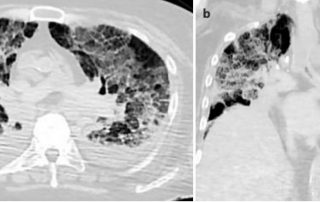

COVID-19 bei alten Patienten

Im Dezember 2019 erfolgten erste Berichte aus der Provinz Wuhan in China über Pneumonien durch einen bis dahin unbekannten Erreger. Als Auslöser konnte rasch SARS-CoV-2 (Severe Acute Respiratory Syndrome Coronavirus 2) identifiziert werden. Seit den ersten Meldungen erfasste die Pandemie 80 Millionen Menschen weltweit, insgesamt kam es bisher zu 1,8 Millionen Todesfällen. Rasch zeigte sich, dass ältere und ganz besonders hochbetagte Menschen das höchste Risiko aufweisen an COVID-19 zu versterben.

COVID-19 überstanden – und dann? UKU startet Forschungsprojekt zu Spätfolgen an Lunge und Herz

Husten, Fieber, Verlust des Geruchs- und Geschmackssinns oder gar schwere Atemnot – diese Symptome treten häufig bei einer COVID-19 Erkrankung auf. Welche bleibenden Schäden COVID-19 hinterlassen kann, ist bisher jedoch kaum erforscht. Nach bisherigen Erkenntnissen müssen 50 % der Erkrankten mit Langzeitfolgen für Lunge und Herz rechnen. Um mehr über die Spätfolgen zu erfahren, hat die Klinik für Innere Medizin II des Universitätsklinikums Ulm (UKU) ein u. a. von Bund und Land gefördertes Forschungsprogramm etabliert, das sich mit den Spätfolgen einer COVID-19 Erkrankung an Lunge und Herz beschäftigt.